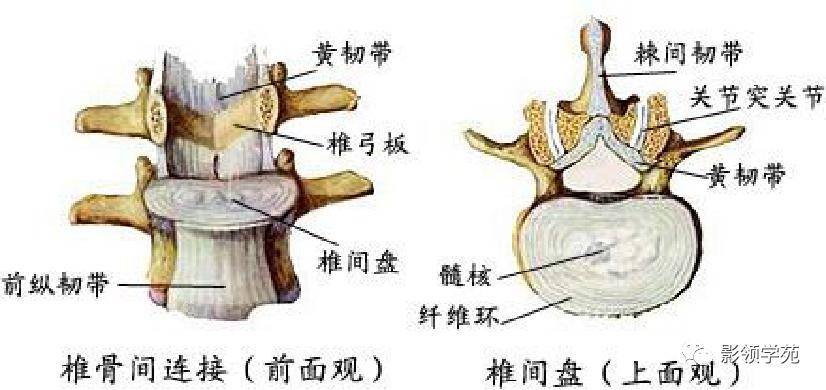

关节与韧带系统

韧带系统

关节与韧带系统

韧带系统